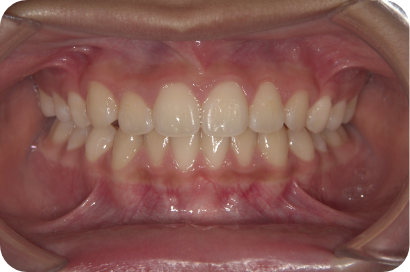

Hさん

Before

After

Sさん

Tさん

- 形態:狭いV型の上顎を丸くて広いU型に改善、歯ならび、咬み合わせの改善

- 機能:咀嚼嚥下トレーニング、口腔周囲筋トレーニング、姿勢改善